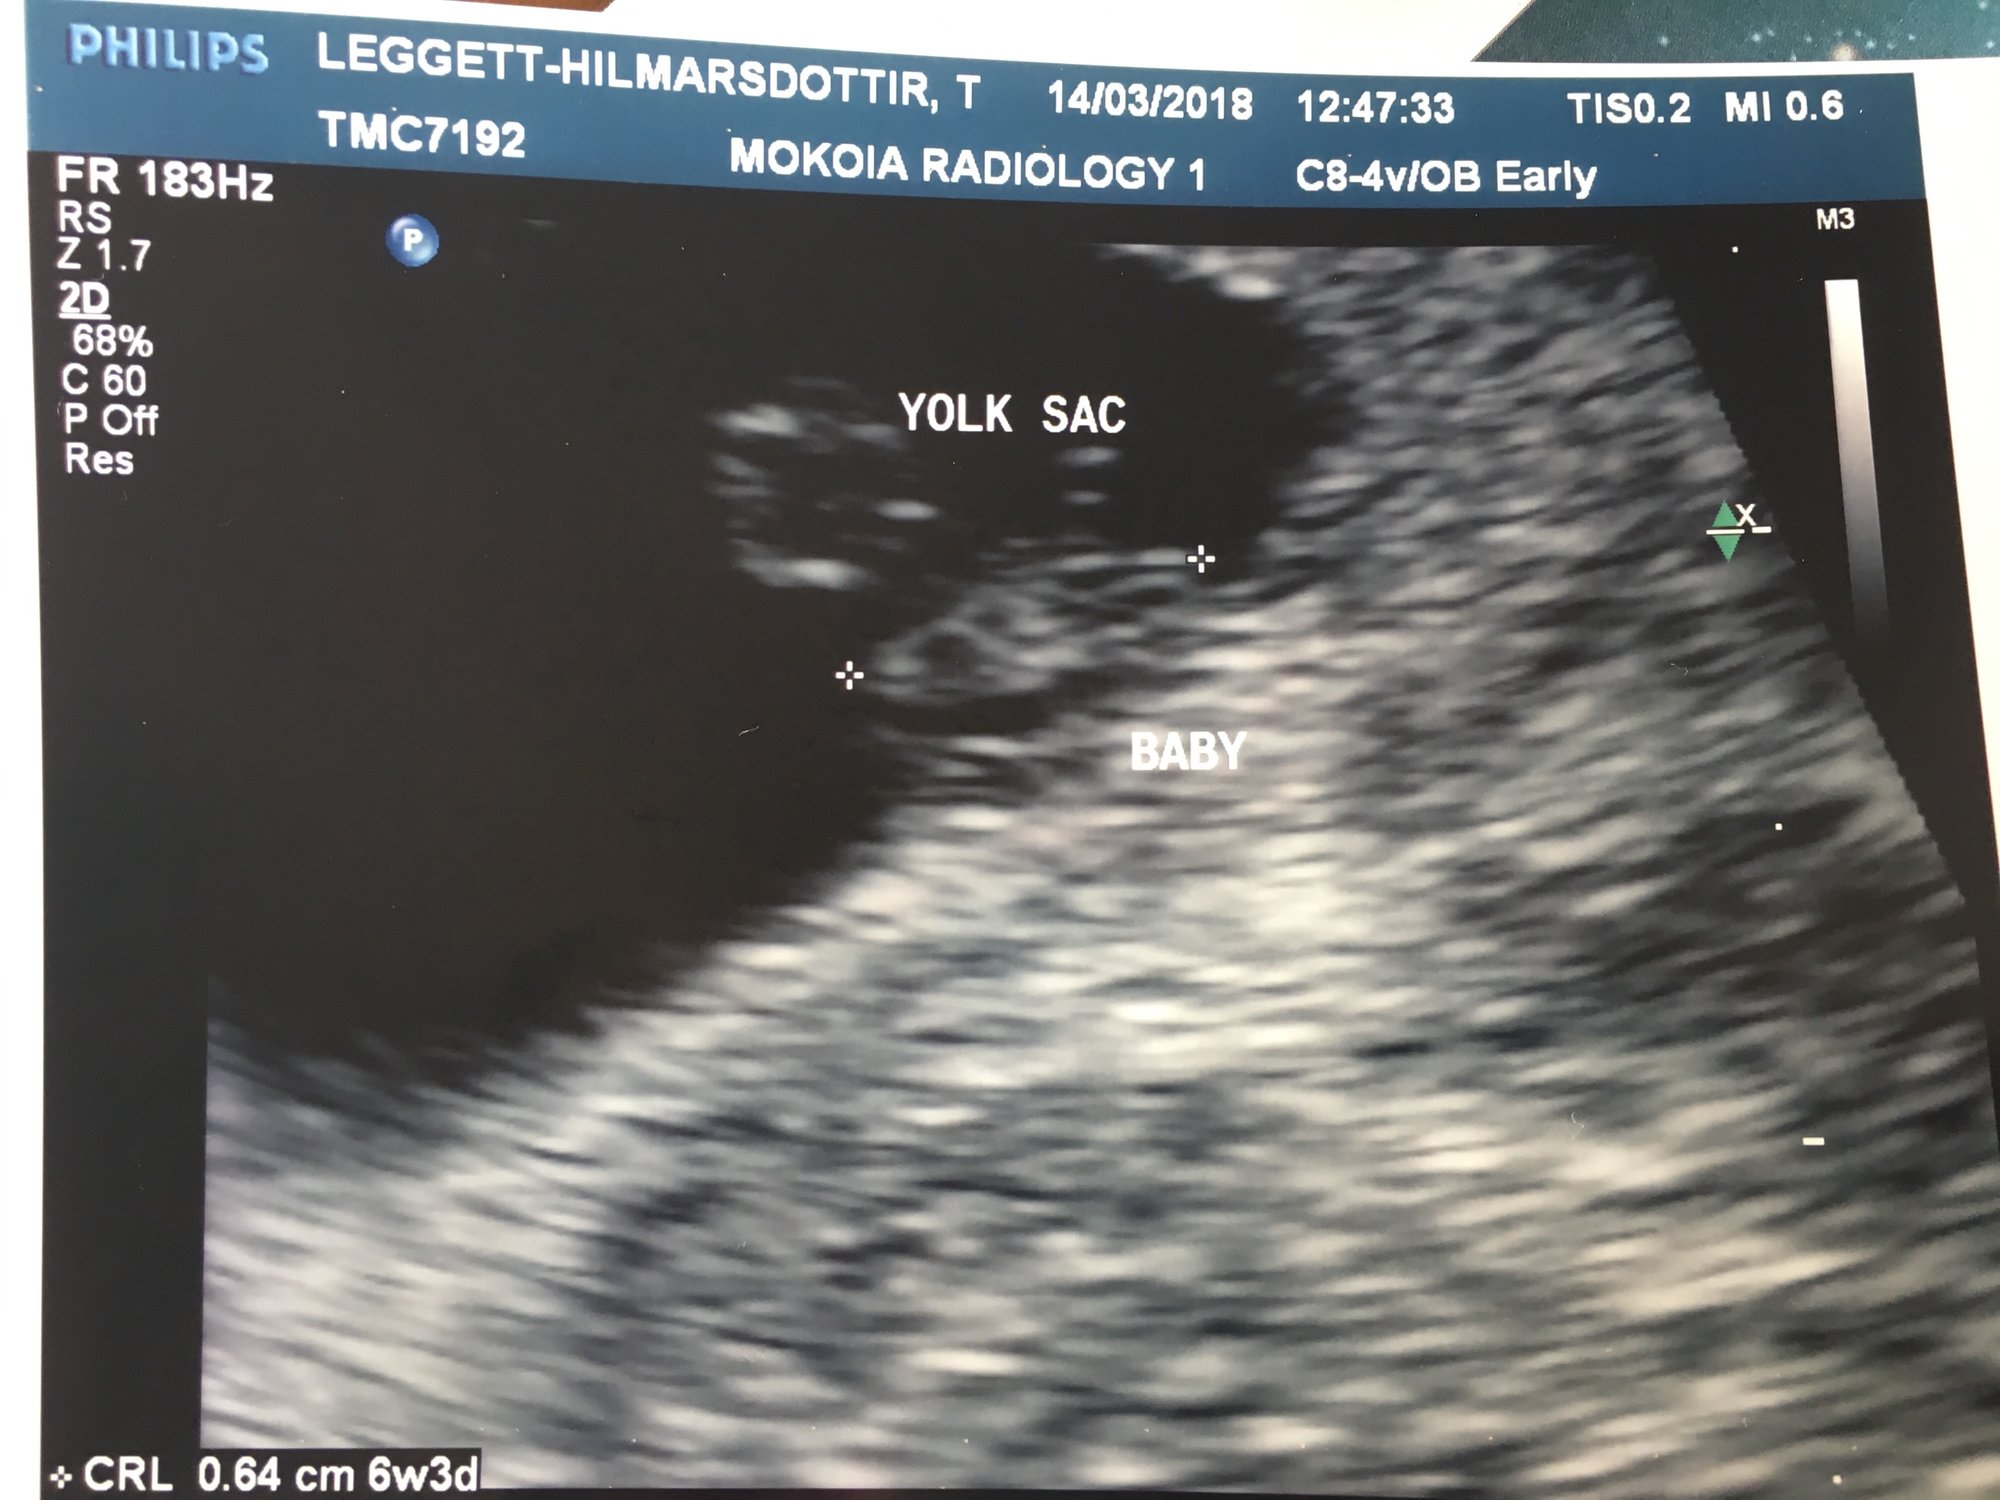

Hi everyone, 6 weeks ultrasound. I’m scheduled back for an 8 weeks ultrasound. Doctor said it’s twins but one is smaller than the other one that we had to wait and see if the other progresses. Has anyone had a similar situation? This is my 3rd pregnancy but first time twins.

• I had my first ultrasound on Monday! I'm not as far along as I thought - I thought I was past 10 weeks but I'll be just 10 weeks tomorrow. So glad I decided to have an early ultrasound - last pregnancy I just had one at 20 weeks. This time around I was having cramping and bleeding and something seemed off. I guess this is why!!!! Seeing double!! They think identical but can't quite be certain yet as I only wanted an abdominal ultrasound this visit. Needless to say I'm freaking out! New due date of November 8th instead of the 3rd...but I'm sure with twins it may be October!